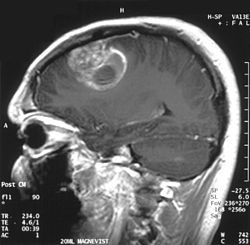

Çalışmanın Odak Noktası: Calgary Üniversitesi araştırmacıları, en agresif beyin kanseri türü olan glioblastomaya karşı, standart tedaviye (ameliyat, radyasyon, kemoterapi) ek olarak yüksek doz B3 vitamini (niasin) kullanımını araştırmaktadır.

Erken Dönem Sonuçları: 24 hasta ile yürütülen klinik denemelerin ilk aşaması oldukça olumludur. Hastaların %82'sinde 6 ay sonrasında hastalığın ilerlemediği görülmüştür. Bu oran, önceki standart tedavi verilerine kıyasla %28'lik dikkate değer bir iyileşme anlamına gelmektedir.

Kafatasının karanlık ve izole ekosisteminde glioblastoma (GBM), bağışıklık sistemini bir avcıdan çok, uyuşmuş bir seyirciye dönüştüren apikal bir predatör gibidir. Makalenin anlattığı hikaye, sadece bir "vitamin takviyesi" değil; hücresel enerji metabolizmasının (NAD+ havuzunun) yeniden inşası üzerinden bağışıklık sisteminin uykudan uyandırılmasıdır.